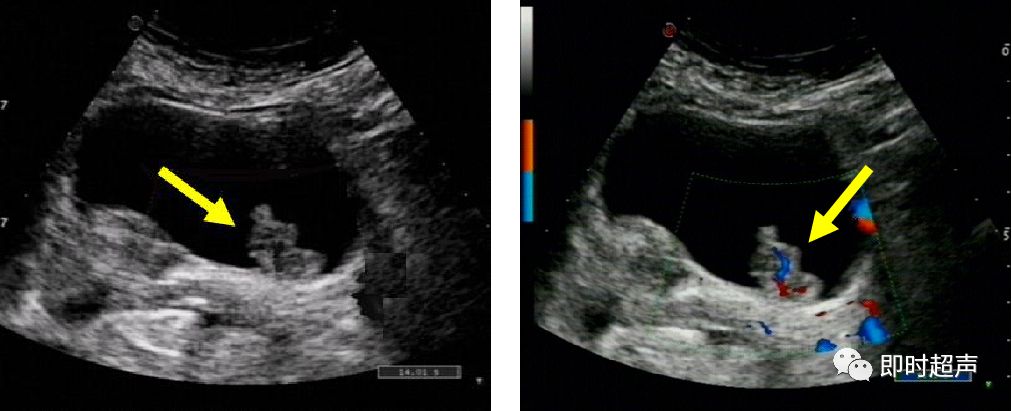

- CDFI:显示肿瘤基底部有细条状血流彩色Doppler频谱显示有动脉频谱:RI>0.60

左图:菜花样团状中、强回声(箭头)

右图:CDFI显示显示肿瘤基底部有细条状血流 (箭头)

膀胱壁实性占位

二维 CDFI